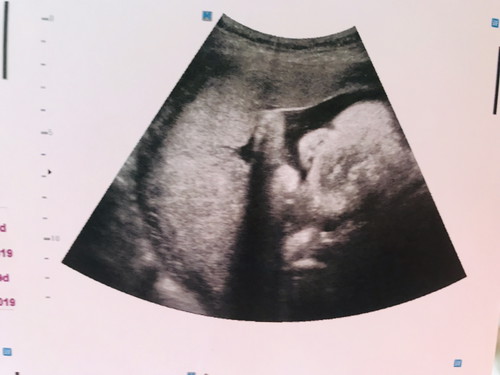

อยากเห็นหน้าลูกชายแล้ววว 36w. นน 3142 แล้วครับผม หน้าผมก็จะกลมๆหน่อย ???